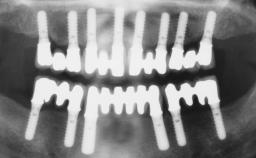

A 65-year-old female patient with a failing residual maxillary dentition and a complete mandibular removable denture was referred for consultation and treatment. The patient’s chief complaint was that her upper residual teeth were mobile and she was unable to chew. The patient also asked us to improve the esthetic appearance of her smile. The patient’s desire was a stable and comfortable dentition in both jaws, and she specifically asked for a fixed rehabilitation. The patient reported a history of recurrent caries, endodontic complications, and periodontal disease as main reasons for previous teeth extractions. The anamnesis was negative for bruxism and TMJ disorders. The patient had no systemic diseases, was not on any medication,and did not smoke. The extraoral examination revealed a medium lip line, a wide diastema between the two central incisors (which, according to the patient, had appeared recently), and a partial collapse of the perioral soft tissues, probably due to loss of the correct vertical dimensions.